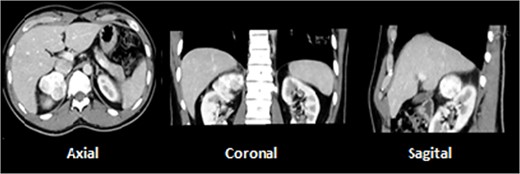

A 28-year-old male with prior history of symptomatic renal lithiasis. During clinical investigation of a persistent right lumbar pain with no other symptoms, a 54 × 43 × 37-mm non-functional adrenal incidentaloma was detected, with an absolute washout of 64% and relative washout of 56%, suggestive of adrenal adenoma (Fig. 2).